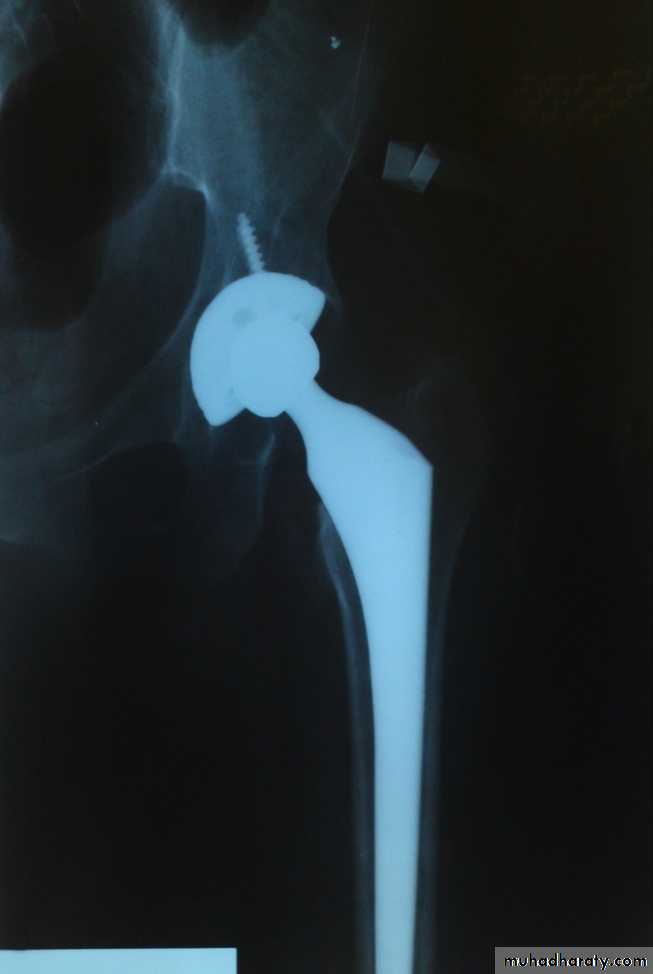

1- avascular necrosis of the femoral head ,appear in the x-ray as an increase in density of the femoral head , but it is not seen before 6 weeks and some time up to 2 years .In early weeks , bone scan and MRI will be helpful in the diagnosis of ischemia .

Treatment of avascular necrosis :

in younger patient treated with realignment osteotomy if it is partial or by arthrodesis of the hip .

In older patient with acetabular changes then total hip replacement .

In patient above 65 years with displaced fracture , partial hip replacement or total hip replacement.

In patients over 45 years old , the treatment is by total hip replacement .Below this age , the treatment will be by realignment osteotomy or arthrodesis .

3- osteoarthritis of the hip joint .

Avascular necrosis of the femoral head will lead to osteoarthritis later on .The treatment is by total hip replacement .